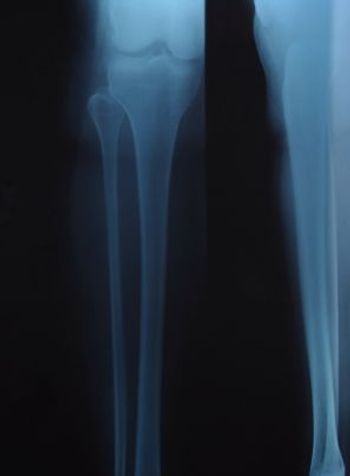

He had bilateral hand pain. History included rheumatic fever, aortic valve replacement, corticosteroid-induced osteonecrosis, and total left hip arthroplasty.